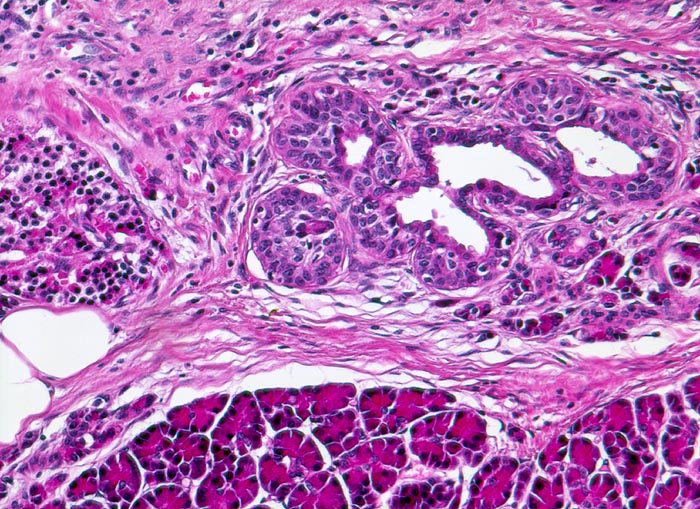

AP/ Chronisch-sklerosierende Pankreatitis

Chronisch-sklerosierende Pankreatitis

Je nach Ursache der chronischen Pankreatitis unterscheidet sich das Muster der Fibrose. Die Nekrosen des interlobulären Gewebes und der interlobulären Gänge bei ethylischen Pankreatitisschüben führen primär zu einer interlobulären Fibrose und interlobulären Gangstrikturen. In den betroffenen interlobulären Gängen führt der Sekretstau zur Konkrementbildung (verkalkte Proteinpräzipitate). Wie bei einer chronisch obstruktiven Pankreatitis kommt es in den unvollständig drainierten Läppchen zu einer Atrophie der Azini verbunden mit intralobulärer Fibrose. Letztere Areale enthalten schliesslich nur noch Reste unregelmässig verteilter Gänge, Inseln, Nerven und Gefässe. In vielen Fällen lassen sich extrapankreatische Pseudozysten gefüllt mit nekrotisch-hämorrhagischem Detritus in der Nachbarschaft der fibrosierten Bezirke nachweisen. Ein Tumor (> 2066), eine Narbe oder einen Stein können als Folge einer Obstruktion des Pankreasganges im Pankreaskopf eine diffuse Atrophie und Fibrose des Pankreas nach sich ziehen. Diese Form wird als chronische obstruktive Pankreatitis bezeichnet und ist gekennzeichnet durch eine deutliche poststenotische Dilatation des betroffenen Pankreasganges ohne Konkrementbildung und eine diffuse Fibrose des an den obstruierten Gang angrenzenden Parenchyms. Bei einer Schädigung des Gangepithels und der Gangwände wie bei hereditärer oder Autoimmunpankreatitis entwickelt sich primär eine periduktale Fibrose. Im Gegensatz zum duktalen Adenokarzinom ist das erhaltene Parenchym bei der chronischen Pankreatitis lobulär angeordnet. Drüsenepithelien zeigen keine Atypien. Karzinomverdächtig sind irregulär infiltrierende atypische Drüsen, atypische Drüsen in unmittelbarer Nachbarschaft von grösseren Gefässen ohne dazwischenliegende Azini, Perineuralscheideninvasion, rupturierte oder inkomplette Drüsen, und Drüsen mit luminalem nekrotischem Detritus.

• Erhaltene Läppchenarchitektur.

• Breite Bänder von sklerosiertem zellarmem Bindegewebe verlaufen zwischen den Läppchen.

• Atrophie des exokrinen Pankreas.

• Erhaltene Inseln und Gangstrukturen.

• Spärliches chronisches Entzündungsinfiltrat.

• Rechts oben ist eine partiell vom Rand her durch Granulationsgewebe organisierte lytische Fettgewebsnekrose erkennbar. Diese ist Folge eines akuten pankreatitischen Schubs.